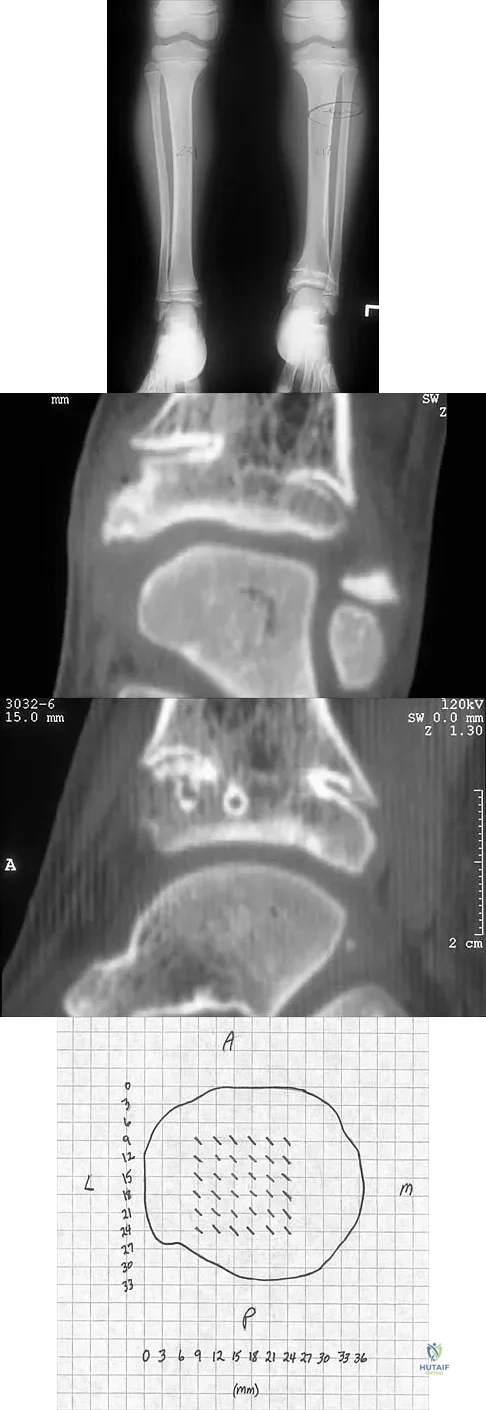

A 5-year-old girl sustained a comminuted Salter-Harris type IV fracture of the left distal tibia 2 years ago. The AP radiograph shown in Figure 54a reveals a growth arrest and a 1.4-cm limb-length discrepancy. The ankle is in approximately 20 degrees of varus. Figure 54b shows a coronal reconstruction image of the distal tibial physis, and Figure 54c shows a sagittal reconstruction image of the same area. On the sagittal reconstruction image, the bar extends from the 9-mm mark to the 24-mm mark in 3-mm increments. On the coronal image, the bar extends from the 9-mm mark to the 24-mm mark, also in 3-mm increments. A map of the physeal bar based on these measurements is shown in Figure 54d. Initial treatment should consist of